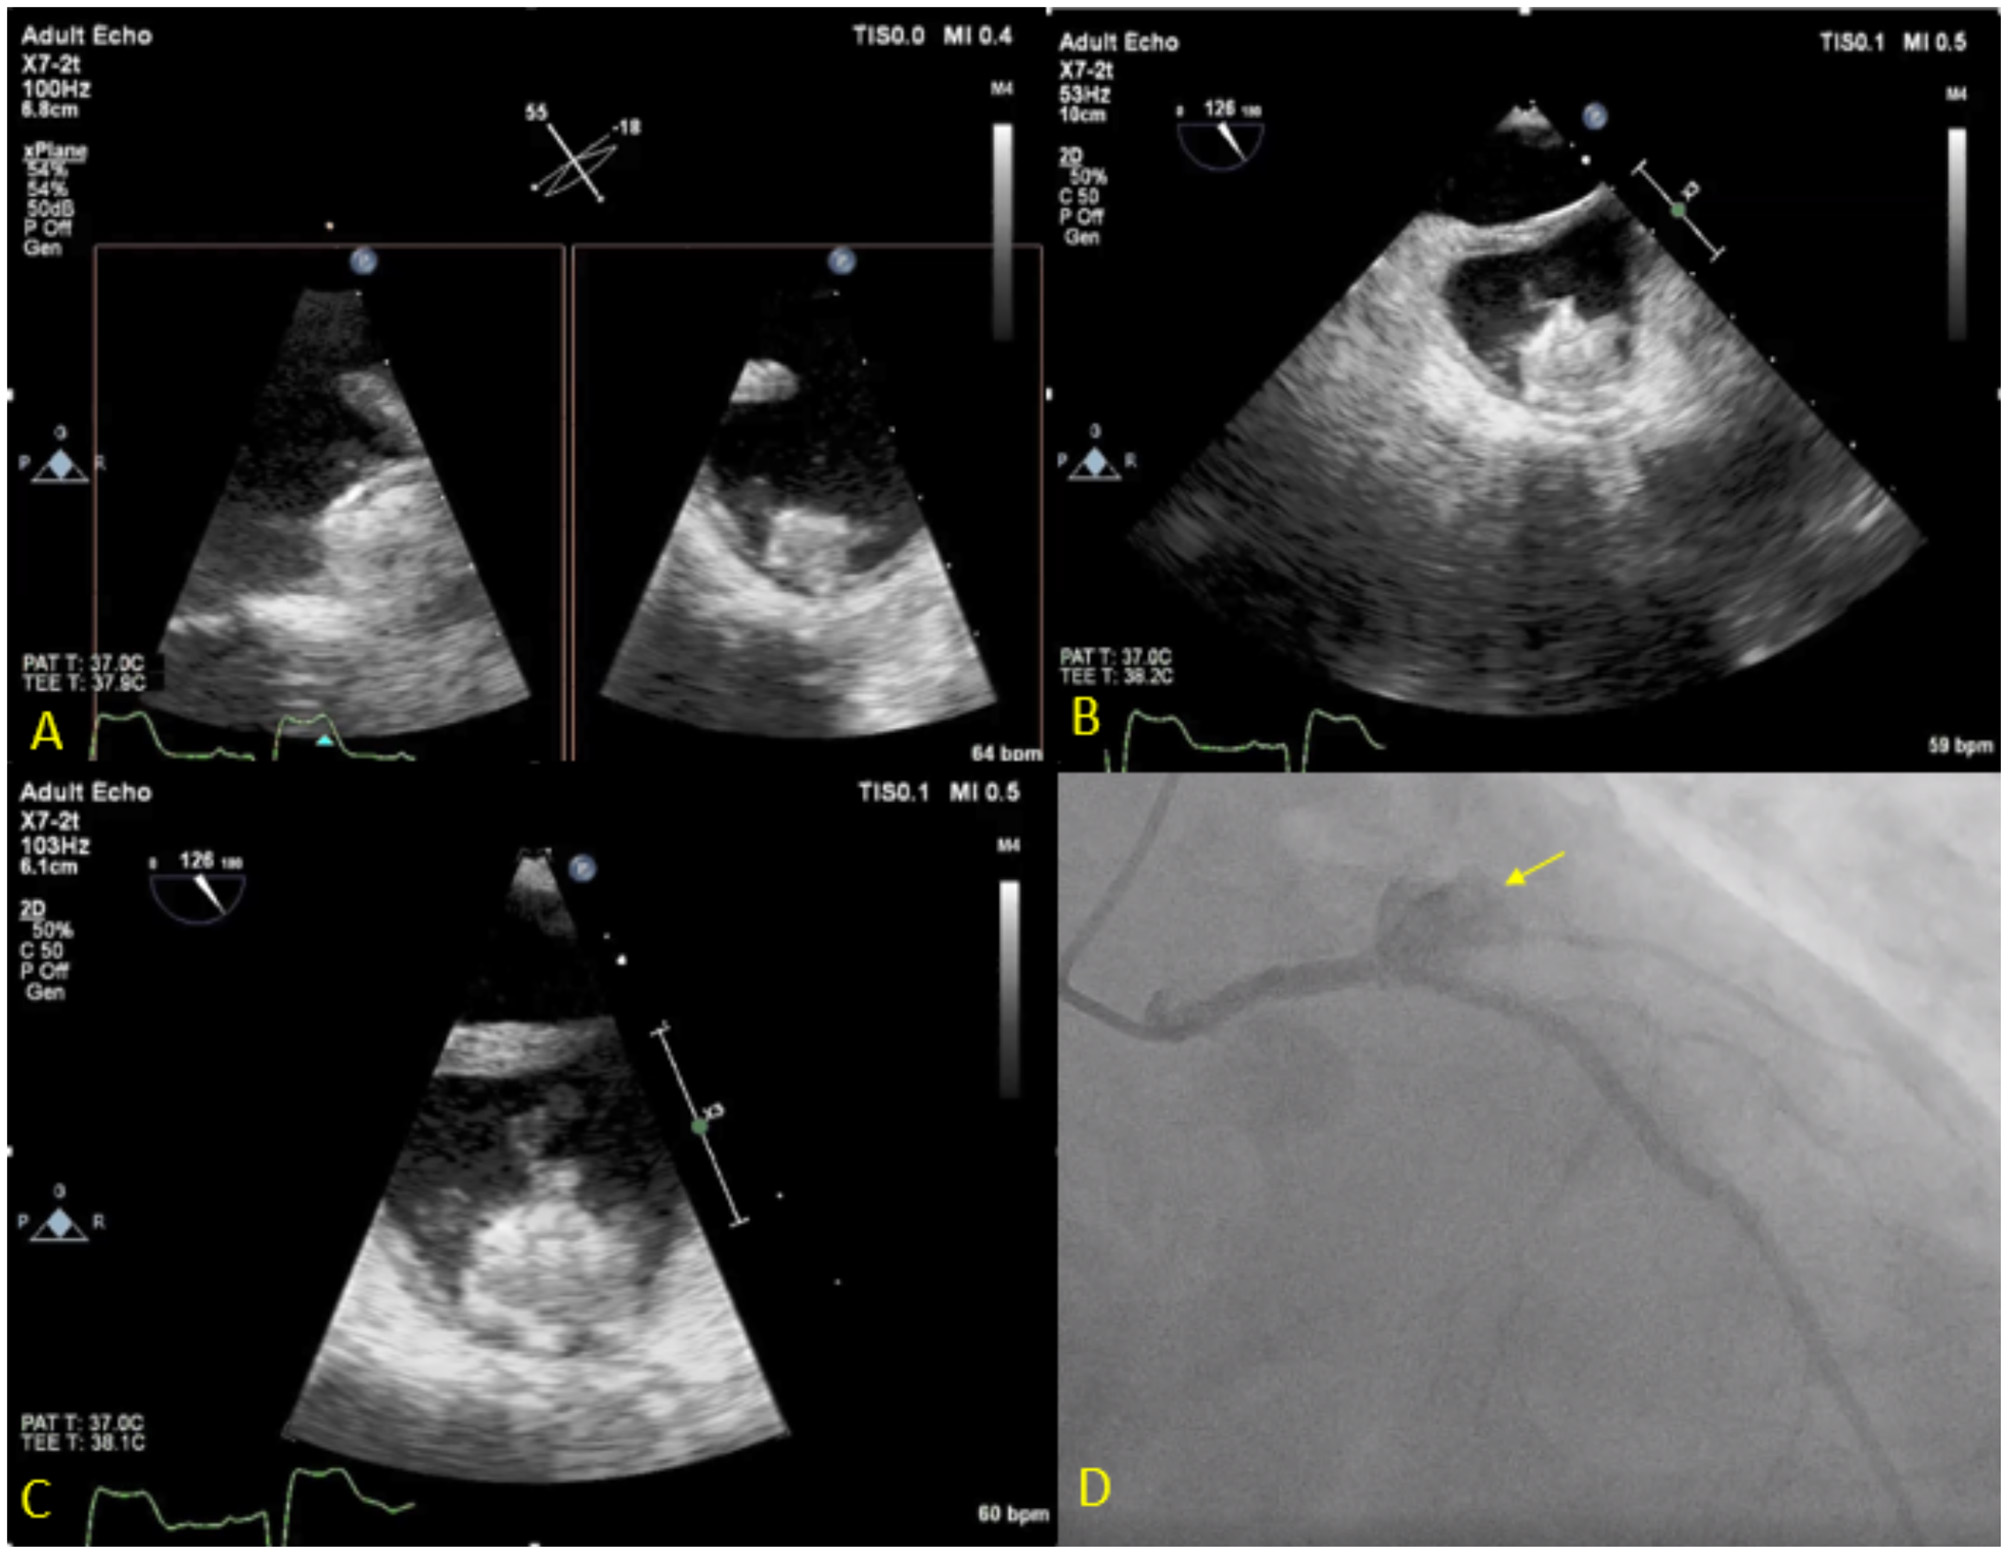

Figure 7

Seventy three year-old male with history of CAD s/p multiple PCIs and Afib s/p Watchman implantation 3 weeks prior to presentation, presented with fever, chest pain and confusion. Blood cultures grew Serratiamarcensens. TEE (A–C) shows Watchman device in the left atrial appendage with large mobile vegetations. Course was complicated by distal embolization to the brain an intestine vasculature. Patient developed worsening chest pain and ST depressions, coronary angiogram (D) shows total occlusion of the proximal left circumflex artery secondary to mycotic aneurysm (Arrow). The patient was deemed too high risk for surgery and was treated medically.